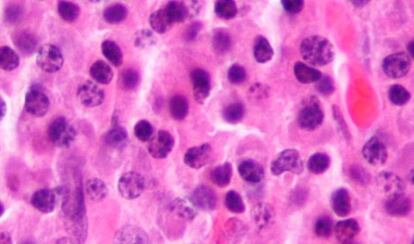

Curiosamente, son los tumores no sólidos, los que no se concentran en un órgano, los que están dando más alegrías en este abordaje. Un nuevo medicamento, el obinutuzumab, ha sido aprobado esta semana por el Ministerio de Sanidad español para tratar la leucemia linfática crónica (LLC), el más común de los tumores hematológicos, que afecta a 30 personas por cada millón de habitantes cada año. Actúa de dos maneras. Se trata de lo que se denomina un anticuerpo monoclonal. Esto quiere decir que está diseñado para unirse específicamente a las células tumorales, como hacen os anticuerpos que reconocen concretamente cada virus o bacteria que infecta un organismo. Una vez establecida la unión, actúa de dos maneras: señala la diana para el sistema inmunitario, y, también, él mismo tiene una cierta acción de destrucción de las células. El resultado es que la capacidad de "negativizar la enfermedad", de curarla, pasa del 3,3% con el tratamiento actual al 37,7%, dijo Francesc Bosch, el hospital Vall d'Hebron, al presentarlo. El riesgo de muerte se reduce un 61% frente a la medicación que se utiliza ahora.

Estos dos son los últimos ejemplos de una línea, la de estimular el sistema inmunitario, que solo acaba de empezar a dar resultados. Los últimos esfuerzos van más al fondo del proceso. "Las células cancerosas no solo se disfrazan para evitar la respuesta inmune. También envían señales para pararla", cuenta Allison que acaba de estar en un congreso de Oncología en la Clínica de la Universidad de Navarra. "Yo digo que le echa el freno". La idea del nuevo abordaje es evitar esa acción. "No se trata tanto de activar la respuesta, como de evitar que se pare", explica.

Ello es así porque los tratamientos dirigidos a las células tumorales antes o después se encuentran con un problema: que estas mutan y se hacen resistentes. Pero al actuar sobre sus señales este inconveniente se evita. "Para una terapia estándar, las mutaciones son malas; en este caso, son buenas", porque si la célula cambia deja de producir moléculas que frenen la respuesta inmune, o la modifica y entonces no tendrán ese efecto, añade Allison.